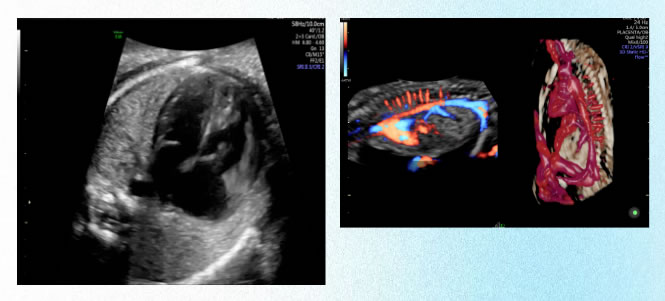

6 胎兒超聲心動圖檢查:孕20-28周

了解胎兒主要心血管結構及大體形態最(zuì)常用的無創醫學影像檢查方法、其臨床應(yīng)用主要目的是檢出致(zhì)命性、預後不良及目(mù)前醫(yī)學不易及不能矯正的嚴重先天性心髒畸形,如單心室、單一大動脈。

超聲產前篩查通過超聲對胎兒進行先(xiān)天性缺陷篩查,是了解(jiě)胎兒主要解剖結構最常用、無(wú)創、可重複的方法。超聲產前篩查的(de)主要目的是(shì)評(píng)估(gū)胎兒生長發育和發現胎兒嚴重(chóng)的結構異常,對降低出生缺陷,提高出生人口素質具有重要意義。